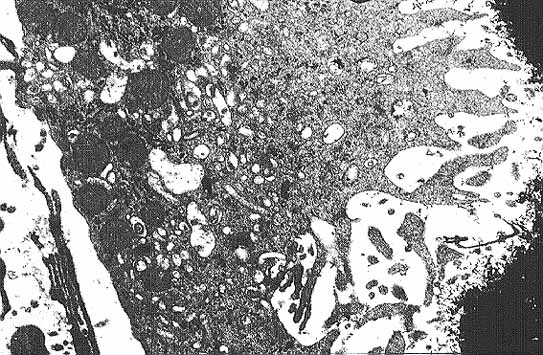

El estudio ultrastructural (Fig.9) de los osteoclastos revela que sus organelas se concentran en el citoplasma perinuclear donde los complejos de Golgi son abundantes2,16. En el resto del citoplasma se observan abundantes mitocondrias y estructuras vesiculares de diversas densidades y tamaños. Es probable que algunas de estas estructuras vesiculares correspondan a lisosomas ricos en TRAP y colagenasas. Las cisternas del retículo endoplásmico rugoso no son muy numerosas ni muy extensas. Es característico de estas células que la zona de su membrana que entra en relación con la matriz ósea se halle fruncida. Entre los plegamientos de la membrana y la matriz ósea existe un estrecho espacio poco denso a los electrones. A ambos lados de la zona de plegamiento la membrana se aplana y se adhiere más intimamente a la matriz. En las tres dimensiones del espacio este segmento aplanado corresponde a un rodete que adhiere el osteoclasto a la superficie ósea de manera parecida a como lo haría el borde de una ventosa. Así, el espacio comprendido entre la membrana fruncida y la matriz ósea queda convertido en un microambiente que se halla aislado del intersticio medular. El segmento de citoplasma adyacente a esta zona aplanada se halla libre de organelas por lo que se denomina zona clara2,16. Esta zona contiene abundantes microfilamentos de actina que probablemente se relacionan con la capacidad de traslación de la célula. De hecho los osteoclastos a medida que reabsorben el hueso realizan un movimiento de vaivén parecido al que efectua el cepillo de un carpintero16. El territorio sobre el que se desplaza un osteoclasto durante el proceso de reabsorción es varias veces superior al de la superficie de la célula y se denomina dominio osteoclástico. La TRAP es capaz de desfosforilar la osteopontina y la sialoproteína ósea por lo que podría facilitar los movimientos de la célula al separarla de estas proteínas de la matriz.

figura9c.jpg (85175 bytes)

Fig. 9 C: Detalle del citoplasma de un osteoclasto. Obsérvese en el margen izquierdo, la membrana fruncida y la solubilización de la matriz ósea de la que se van desprendiendo pequeñas espículas de color negro. En el margen derecho del citoplasma, se observan numerosas mitocondrias y el resto se halla ocupado por vesículas de diversos tamaños, algunas de las cuales podrían ser de origen lisosómico (Microsopía electrónica de transmisión x 7100).